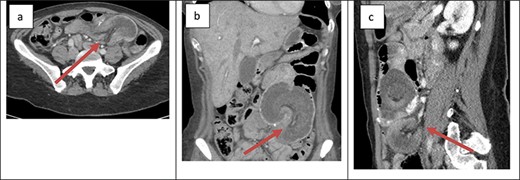

The second patient was a 41-year-old female with a history of open Roux-en-Y gastric bypass ~20 years prior and abdominoplasty with bilateral breast augmentation. Her only medication was Contrave to treat weight regain after bariatric surgery. She was 400 lbs at the time of her surgery and 185 lbs at time of presentation. The patient presented with an 8-h history of severe abdominal pain. The patient also reported two episodes of vomiting and two bowel movements prior to presentation. Her vitals were within the normal limits and laboratory work was unremarkable. Physical examination revealed a soft abdomen with a palpable mass at the site of tenderness in the left lower quadrant. Cross-sectional imaging revealed retrograde intussusception at the jejunojejunal anastomosis (Fig. 2); the cross-sectional imaging was also suggestive of hepatic vein thrombosis that was ruled out with a hepatic duplex ultrasound. The patient was taken emergently to the operating room for laparoscopic lysis of adhesions and reduction of intussusception. The involved small bowel measured ~30 cm in length and appeared grossly viable so no formal resection or revision was performed at the time of operation. The patient’s post-operative course was uncomplicated. She was started on clear liquids on POD#1 and discharged home on POD#2. The patient reported that she was symptom free at her 1-week post-operative office appointment.

Cross-sectional imaging of displaying bowel and mesentery (arrow) intussuscepting into the JJ anastomosis on (a) transverse view, (b) coronal view and (c) sagittal view.

The presentation of intussusception is widely variable depending on the severity of the disease process. Common presentations include abdominal pain, nausea and vomiting, new palpable abdominal mass, lower GI bleeding and signs of sepsis. Intussusception can be diagnosed through various imaging modalities such as cross-sectional imaging, plain radiographs, small bowel series and ultrasonography. Cross-sectional imaging is believed to be not only highly sensitive but also reliable [3]. On cross-sectional imaging, intussusception appears as a complex soft tissue mass representing bowel telescoped onto itself often with an eccentric area of hypoattenuation within the mass representing the intussuscepted mesenteric fat [5]. The pathognomonic appearance is appreciated in Figs 1 and 2. Furthermore, the wall of the internalized loop of bowel can be observed within the dilated bowel when imaging is enhanced with intravenous contrast. Prompt diagnosis and surgical intervention are paramount in management of intussusception.